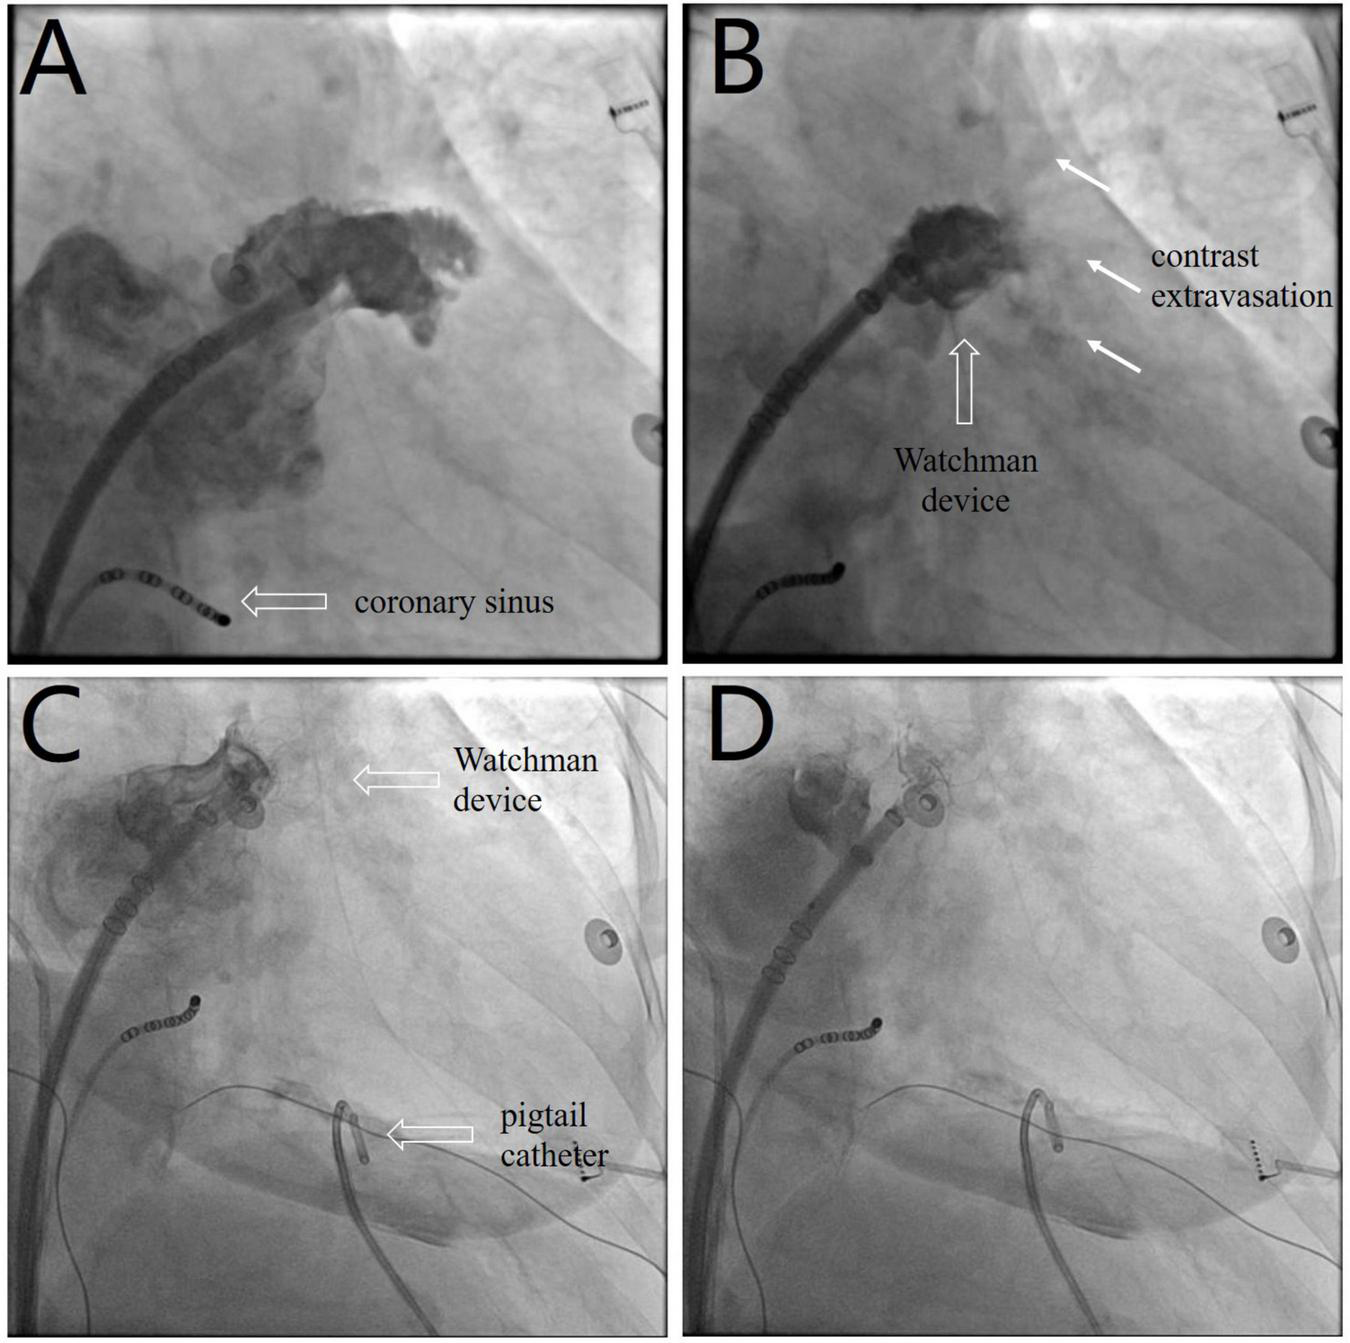

FIGURE 1

(A) Left atrial appendage angiography before device selection (Supplementary Video 1). (B) Post-deployment angiography shows brisk contrast extravasation (white arrow) into the pericardial space (Supplementary Video 2). (C) The device is redeployed at a more proximal position to seal the appendage and distal perforation (Supplementary Video 3). (D) The device is released after confirmation of device stability and the absence of residual peri-device leakage (Supplementary Video 4).

The LAAC procedure was performed under local anesthesia, deep sedation, and fluoroscopic guidance. A decapolar catheter was inserted through the right femoral vein into the coronary sinus to guide transseptal puncture. Unfractionated heparin (100 U/kg) was administered immediately following transseptal puncture to achieve an activated clotting time of 330 s. The left atrial pressure was 33/15 mmHg. Left atrial appendage (LAA) angiography (Figure 1A and Supplementary Video 1) at the right anterior oblique 30° and caudal 20° view revealed ostial width of 19.5 mm and depth of 21.8 mm. A 24-mm Watchman device (Boston Scientific, MA, United States) was selected and then deployed under fluoroscopic guidance. Post-deployment angiography revealed brisk contrast extravasation into the pericardial space (Figure 1B and Supplementary Video 2). The patient rapidly developed cardiac tamponade, and blood pressure decreased from 131/72 to 78/35 mmHg.

We performed emergency pericardiocentesis via a subxiphoid approach under fluoroscopic guidance. A pigtail catheter was inserted into the pericardial cavity to drain blood, and the aspirated pericardial blood was immediately returned to the femoral vein via a sheath. Protamine (30 mg) was simultaneously administered to reverse heparin activity. The patient’s systolic blood pressure returned to 95 mmHg after aspiration of 150 ml of blood. The device was retracted and redeployed at a more proximal position to effectively seal the LAA and distal perforation (Figure 1C and Supplementary Video 3). After confirmation of device stability and absence of residual peri-device leakage, the Watchman device was released (Figure 1D and Supplementary Video 4). Repeat aspiration was performed for an additional 15 min. The patient’s vital signs stabilized, and blood pressure returned to 120/65 mmHg. The pericardial fluid was drained to dryness after aspiration of 400 ml of blood, and minimal pericardial fluid reaccumulation was observed.